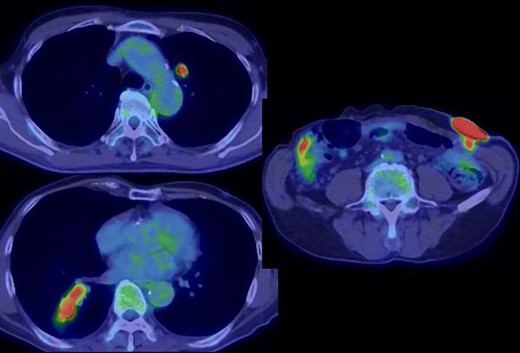

Positron emission tomography revealed abnormal accumulation of a mass in the left abdominal wall (with a maximum standardized uptake value [SUVmax] of 38.7) and slight accumulation of a mass in the S10 (SUVmax 5.7) and S1/2 (SUVmax 5.5) regions (Fig. 5), but no abnormal accumulation in the abdominal cavity was found. Biopsy of the abdominal wall mass revealed highly- to moderately-differentiated ductal adenocarcinoma cells. Immunostaining was strongly positive for CDX2/CK20 and negative for CK7 (Fig. 6), suggesting adenocarcinoma of intestinal origin. Transbronchial biopsy of the lung mass was also positive for CDX2/CK20 and negative for CK7/TTF-1/napsin A. The tumor cells had an eosinophilic cytoplasm and small nuclei of unequal sizes, similar to the histology of the biopsy specimen of the previously described abdominal wall mass.

Positron emission tomography revealed an abnormal accumulation of a mass in the abdominal wall and bilateral lung.